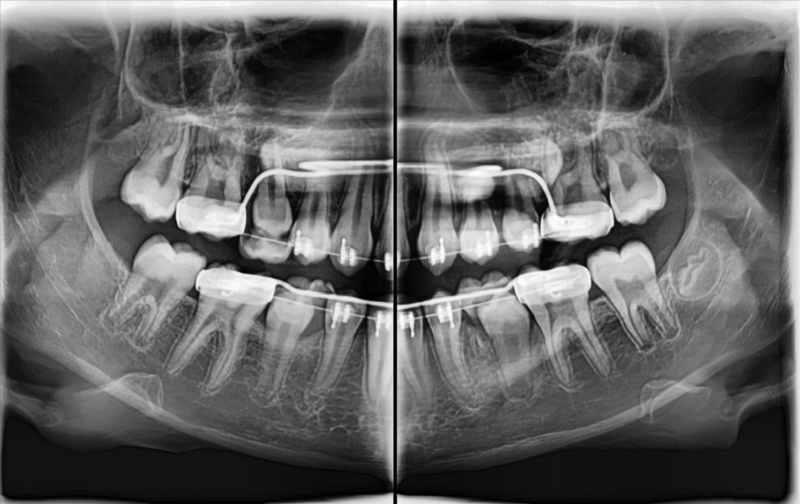

Dokładne obrazy 2D i 3D – niezbędne w chirurgii, ortodoncji, endodoncji i laryngologii

Zakres obrazowania – od pojedynczego zęba po całą czaszkę

Zdjęcie panoramiczne pokazuje całe uzębienie i kości szczęki oraz żuchwy, ujawniając zmiany niewidoczne na RTG punktowym (torbiele, guzy, zapalenia, zwyrodnienia stawów). To badanie profilaktyczne, zalecane co 2 lata.